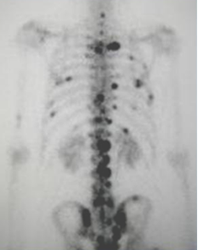

Gamagrama óseo con múltiples metástasis a arcos costales y columna

Gamagrama óseo con metástasis múltiples por cáncer de próstata